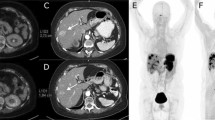

The interval between administration of lanreotide and the PET scan was registered for all 35 scans. Here the average time of lanreotide injection before the scan was 14.01 ± 9.0 days. To investigate the effects of the time-interval on the biodistribution, two groups of patients were considered depending on the time of lanreotide injection (within 5 days or more than 5 days prior to the scan). There was a significantly higher tracer availability within the blood when the tracer was injected within 5 days prior to the scan (SUVmax bloodpool < 5 days 1.78 ± 0.48 vs > 5 days 1.37 ± 0.44, p = 0.02, see Fig. 3). However, this effect was not significant for the visceral organs or the tumours (Fig. 4). Here, a patient was scanned twice after treatment with lanreotide after 21 days of injection (follow-up 1) and a half year later after 3 days of lanreotide injection (follow-up 2). In the same subject, the intensity of the tracer accumulation in the background was lower at 3 days after injection (also quantified in Fig. 4), when compared to 21 days. Liver somatostatin receptor binding intensity was half the intensity after 3 days, when compared to 21 days after injection, also resulting in higher tracer availability in the blood. Tumor intensity on the scan was slightly higher, but normalized after correction of liver accumulation. Other parameters were similar.

Example of a patient scanned twice after lanreotide treatment with first follow-up scan 21 days after lanreotide injection and the second scan after 3 days of lanreotide injection (interval between the scans is approximately 6 months). A visual and quantifiable difference between scans can be found in visceral and bloodpool availability of the tracer, in this case resulting in a difference in tumor uptake of the tracer